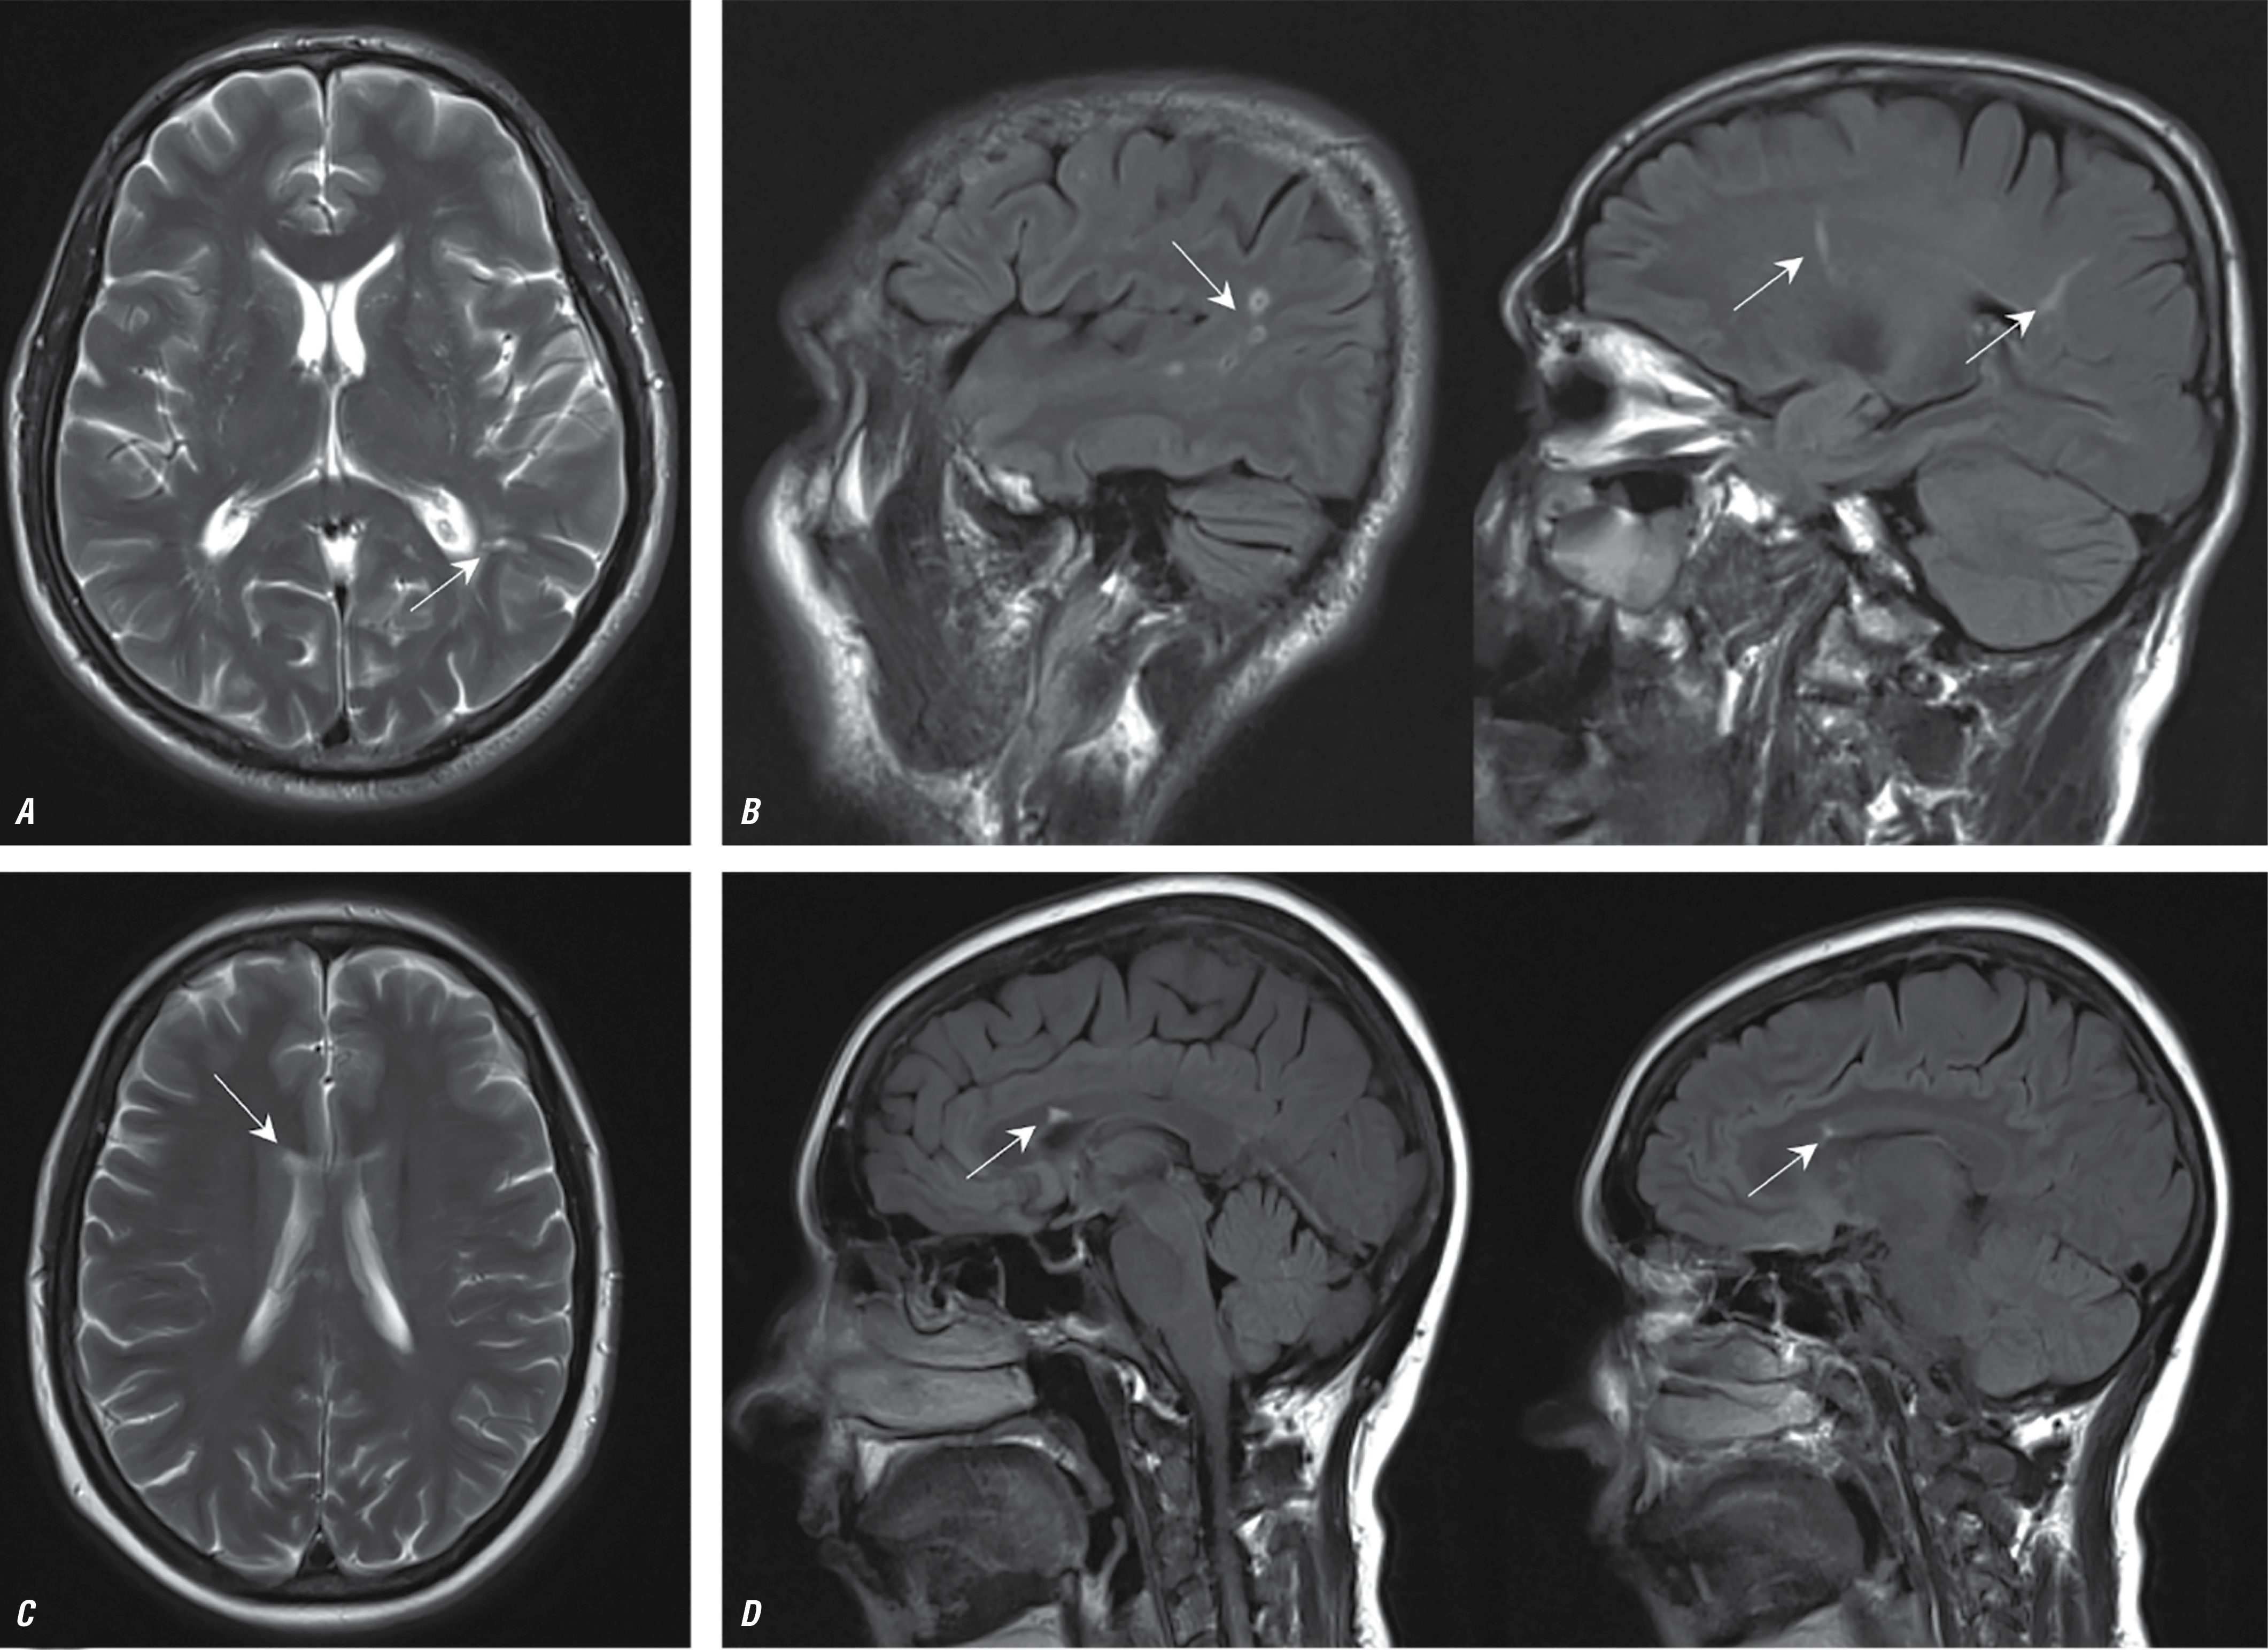

Первичный миелофиброз

Характерными клиническими признаками НМК на фоне ПМФ у большинства обследованных являлись рецидивирующие преходящее онемение в руках/ногах, неловкость при выполнении мелких движений, самостоятельно купировавшиеся в течение нескольких часов по типу транзиторной ишемической атаки. Часть пациентов описывала эпизоды транзиторной ишемической атаки в течение нескольких недель, месяцев до развития НМК. Несколько пациентов отмечали приступы выраженной, атипичной головной боли с появлением ауры (в виде «ряби» перед глазами, изменения цветоощущения), с последующим развитием очаговых изменений (в течение нескольких недель).

Средний возраст пациентов с инсультом на фоне ПМФ составлял 50 лет, ни в одном случае постинфарктные изменения не приводили к стойкой утрате трудоспособности с выраженным двигательным дефицитом.

Один пациент после постановки диагноза ПМФ не принимал циторедуктивную, антитромботическую терапию (отсутствие тромбозов в анамнезе, возраст менее 60 лет), однако через 7 лет после постановки диагноза ПМФ развилось НМК в бассейне правой средней мозговой артерии. У другого пациента постановке асимптомно протекавшего гематологического диагноза предшествовало НМК.

Основным паттерном постинфарктных изменений у пациентов с ПМФ при нейровизуализации являлись небольшие очаговые поражения в глубоких отделах вещества мозга, вероятнее всего, после развития НМК по типу гемореологической микрооклюзии (рис. 5).

Рис. 5. МРТ головного мозга пациентов с ПМФ в аксиальной проекции в режиме Т2 (А, С) и в сагиттальной проекции в режиме Т2-FLAIR (B, D).

Визуализируются небольшие постинфарктные перивентрикулярные очаги (указаны стрелками).

Fig. 5. Brain MRI of patients with PMF in axial T2 images (А, С) and in sagittal T2 FLAIR images (B, D).

Small post-infarction periventricular lesions are visualized (as indicated by arrows).